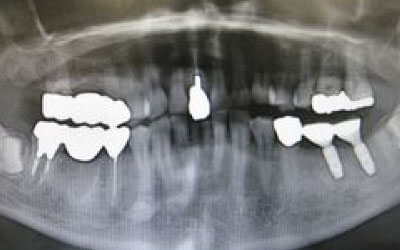

CTでは、骨や歯の状態を3Dで確認でき、正確な距離の測定も行えます。

骨の厚さや傾き、神経の位置などを事前にしっかりと測定することで、安全にインプラントを行うことができます。